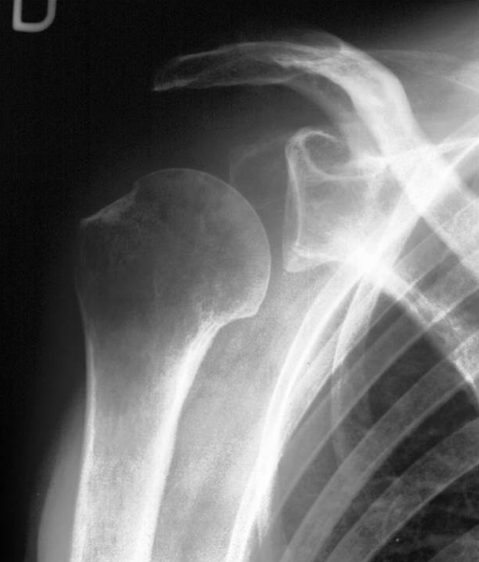

12

Q

What is the diagnosis?

What are some lesions associated with this injury?

A

Anterior shoulder dislocation

Associated with:

• Hill-Sach fracture (60%)

• Flap fracture (15%)

• Bankart lesion

• Labral tear

axillary nerve injury possible